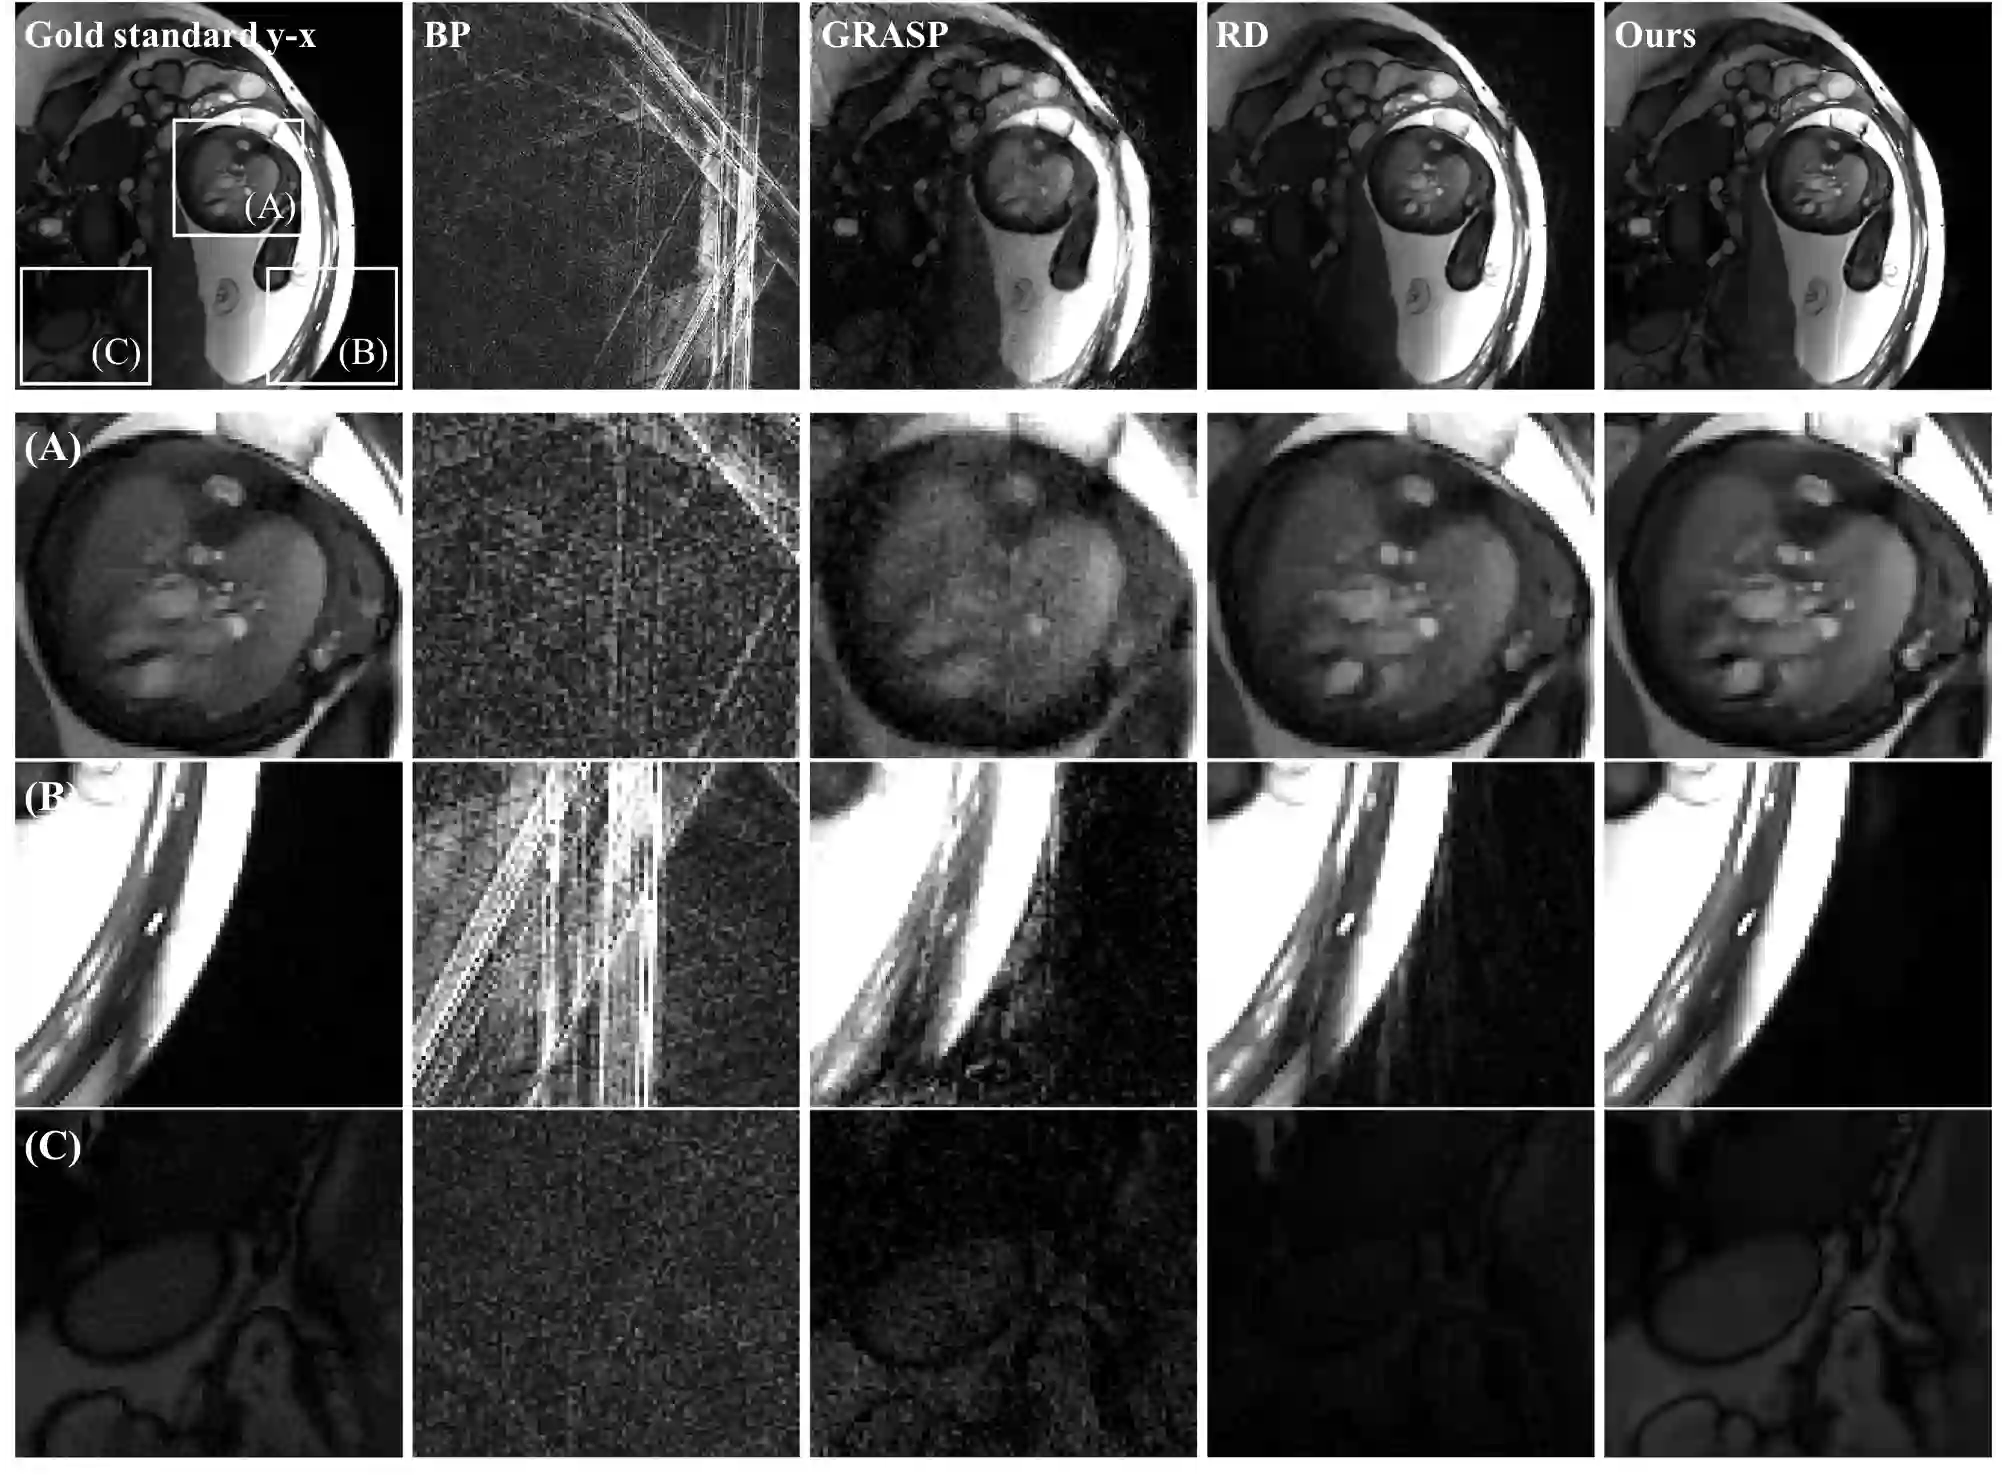

We propose a novel unsupervised deep-learning-based algorithm for dynamic magnetic resonance imaging (MRI) reconstruction. Dynamic MRI requires rapid data acquisition for the study of moving organs such as the heart. Existing reconstruction methods suffer from restrictions either in the model design or in the absence of ground-truth data, resulting in low image quality. We introduce a generalized version of the deep-image-prior approach, which optimizes the network weights to fit a sequence of sparsely acquired dynamic MRI measurements. Our method needs neither prior training nor additional data. In particular, for cardiac images, it does not require the marking of heartbeats or the reordering of spokes. The key ingredients of our method are threefold: 1) a fixed low-dimensional manifold that encodes the temporal variations of images; 2) a network that maps the manifold into a more expressive latent space; and 3) a convolutional neural network that generates a dynamic series of MRI images from the latent variables and that favors their consistency with the measurements in k-space. Our method outperforms the state-of-the-art methods quantitatively and qualitatively in both retrospective and real fetal cardiac datasets. To the best of our knowledge, this is the first unsupervised deep-learning-based method that can reconstruct the continuous variation of dynamic MRI sequences with high spatial resolution.